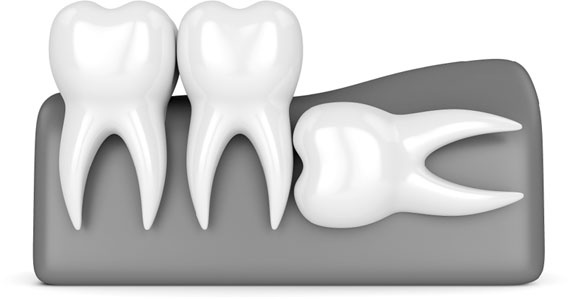

Вот, например, какая «восьмерка» была у меня:

Иллюстрация к книге — Злые зубы [i_033.jpg]

Если на снимках зубы мудрости расположены криво, есть смысл удалить их до окончательного формирования корневой системы.

Удаление было довольно легким из-за того, что корень до конца не сформирован. А вполне возможно, что если бы я подождала еще пару лет, выросло бы что-нибудь такое и удалить это было бы гораздо сложнее: